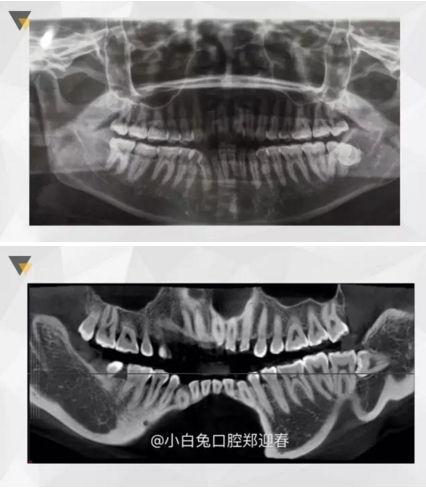

阻生齒外科聯(lián)合正畸治療

24.png

25.png

26.png

27.png

28.png

來源:小白兔口腔鄭穎春